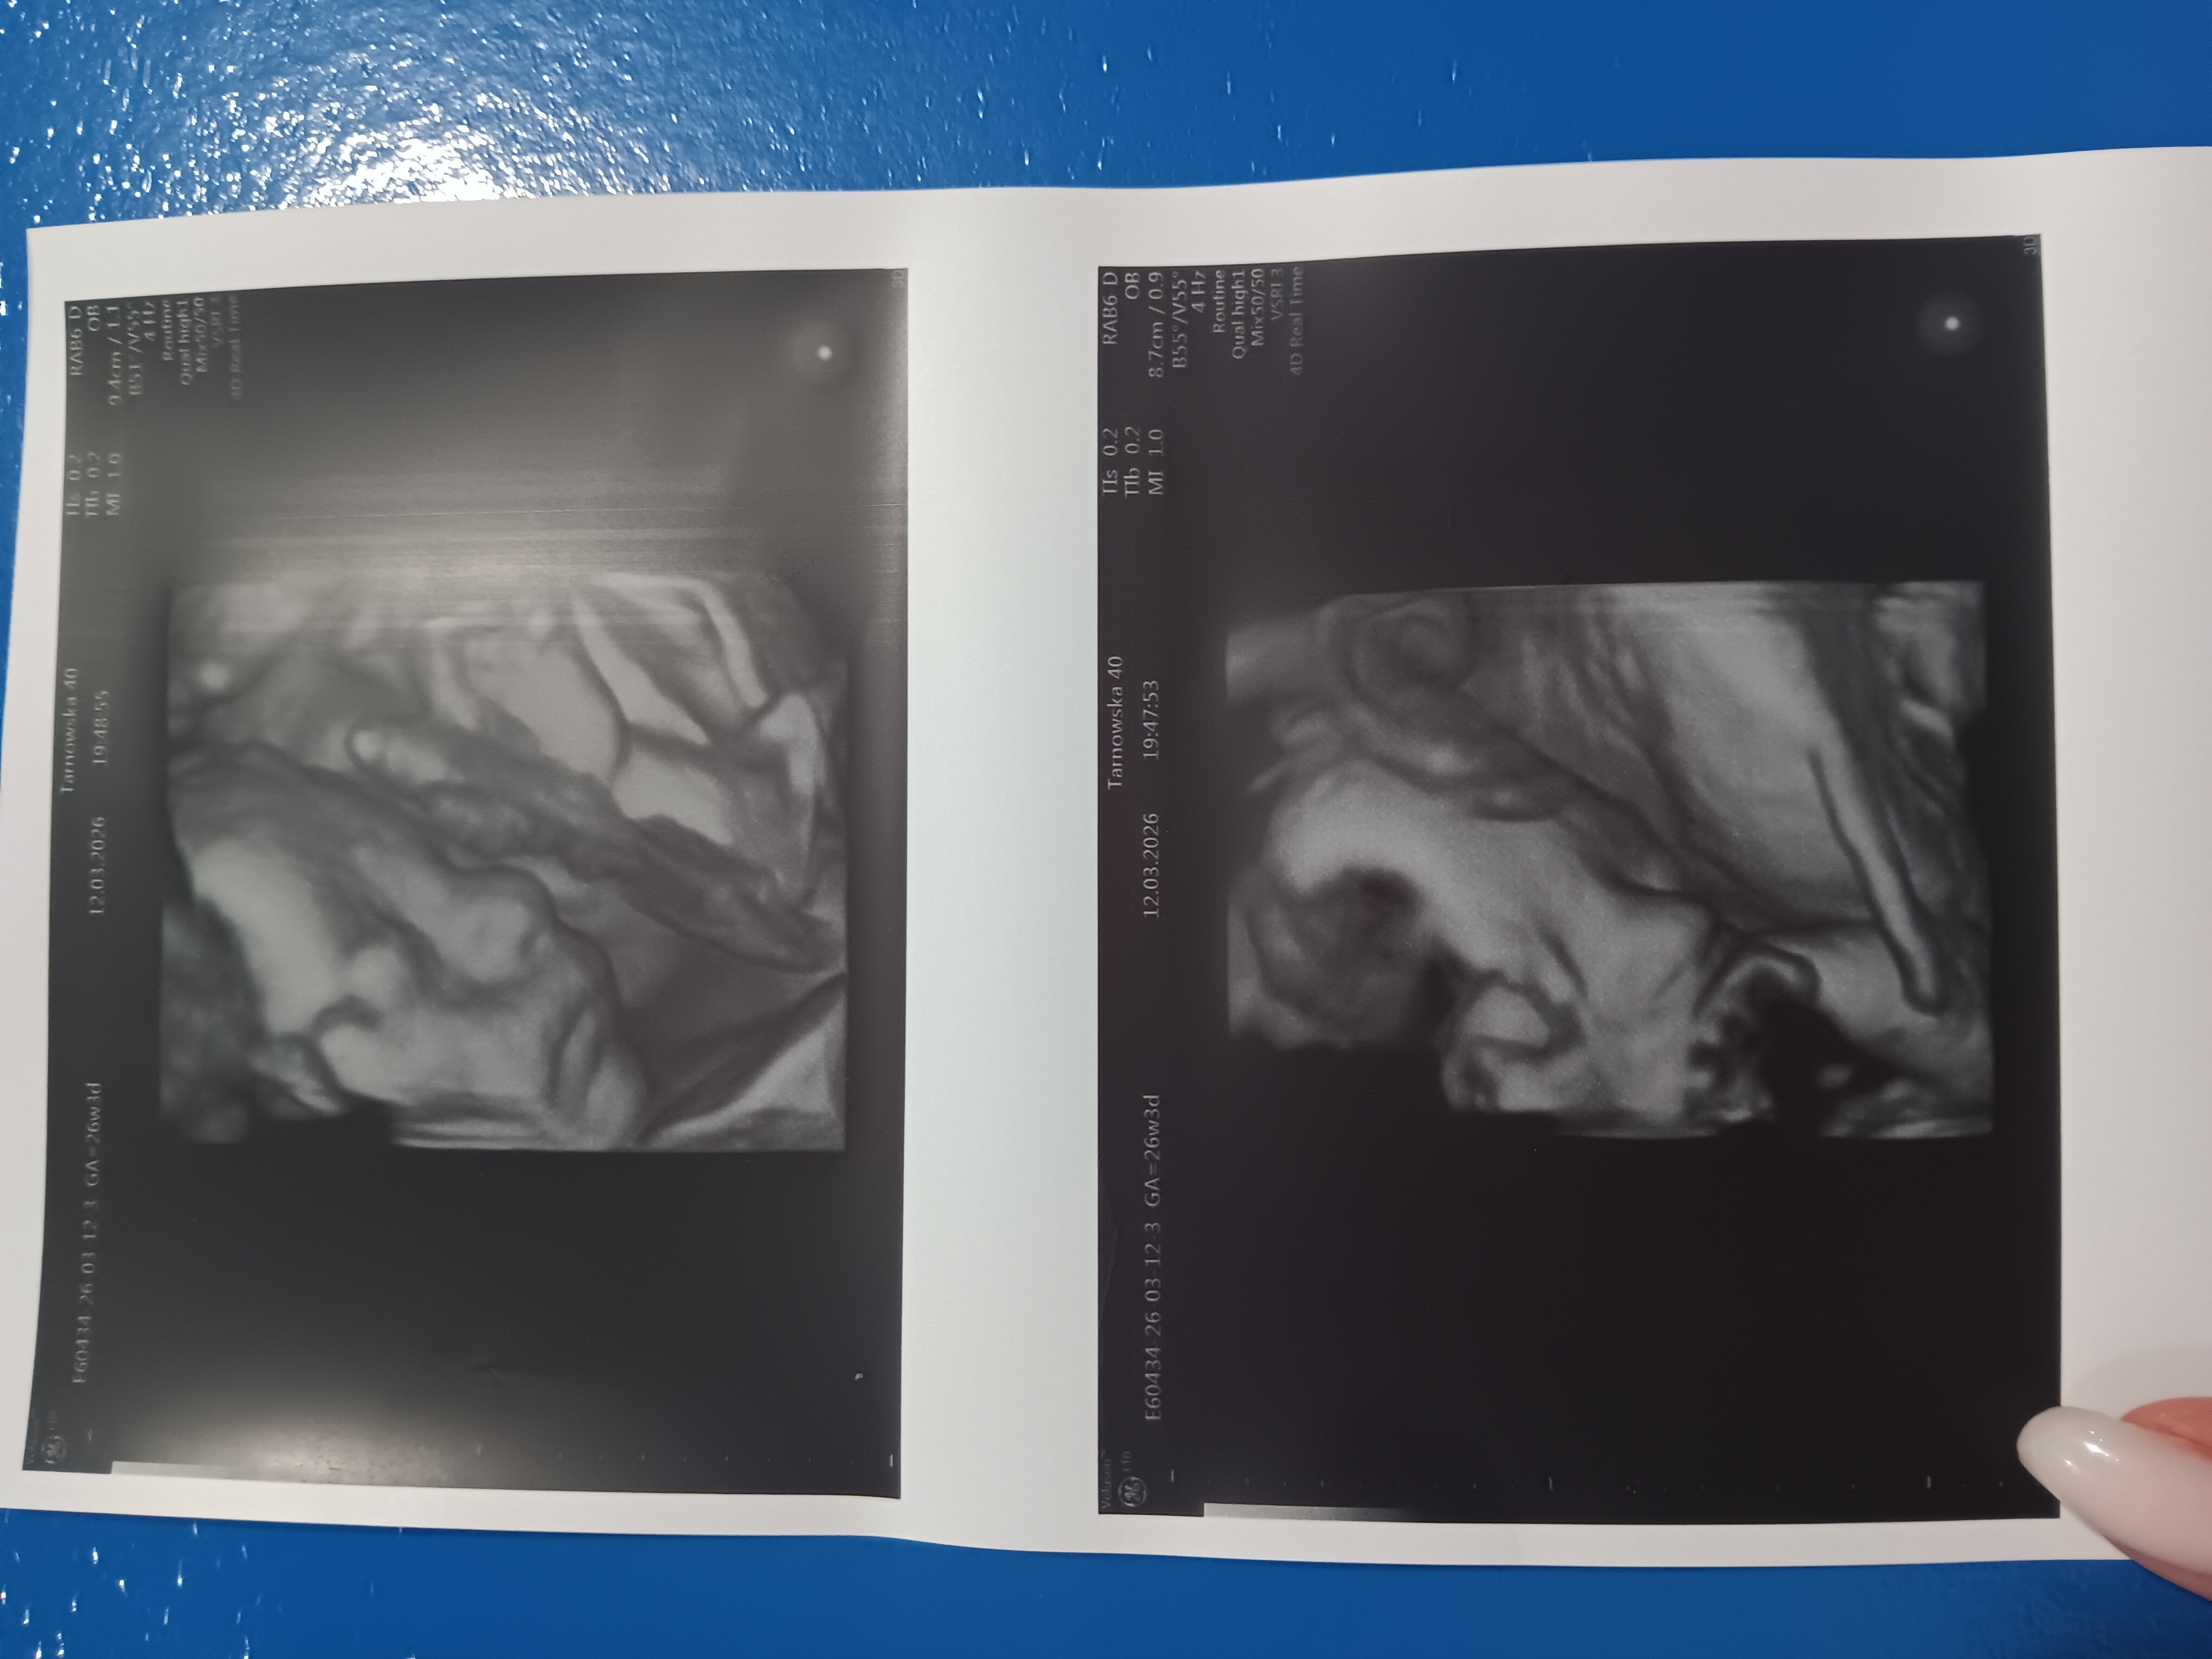

U nas po wizycie wszystko dobrze, wskaźniki ładnie po środku. Oliwier jak nigdy spał i nie był zadowolony , zasłonił buzię pępowiną i ręką, na chwilke tylko buziunię pokazał. Dr walczyla ile mogla, abyśmy wyszli z jakimś zdjęciem.

Matka tyje, a syn trzyma formę 915g . Czyli waga tez w normie Także nie doczekaliśmy przekroczenia magicznego kg.